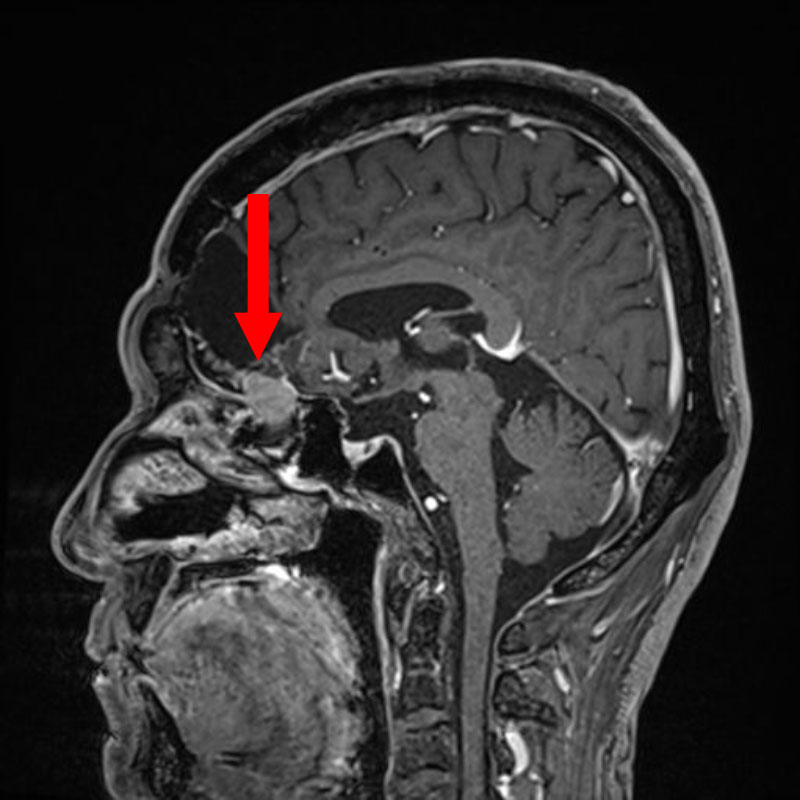

断層撮影

手術前1

手術前2